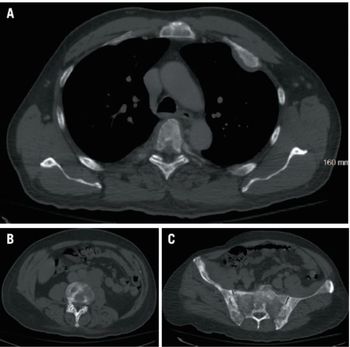

Mehmet Sitki Copur, MD, and colleagues examine the case of a 65-year-old patient with appendiceal mucinous neoplasms of the appendix who was treated with cytoreductive surgery and hyperthermic intraperitoneal chemotherapy.

ABSTRACT Gastrointestinal stromal tumors (GISTs) are rare neoplasms of the gastrointestinal tract. They commonly present with nonspecific symptoms and thus are often discovered incidentally. They are best identified by CT scan and most stain positive for CD117 (C-Kit), CD34, and/or DOG-1. Several risk stratification classification systems have been developed based on tumor size, mitotic rate, location, and perforation. Traditional chemotherapy and radiation therapy have been very ineffective, making surgery the mainstay of treatment. The discovery of mutations associated with these tumors has revolutionized the treatment approach. Imatinib mesylate, a selective tyrosine kinase receptor inhibitor, used as adjuvant or neoadjuvant therapy, has greatly improved the morbidity and mortality associated with GISTs. As the survival of patients has increased with the long-term use of targeted therapies, quality-of-life issues now have become much more relevant and have come to the forefront of care. We present a young woman who was successfully treated for GIST but now faces associated long-term adverse effects of imatinib, including the challenge of preserving fertility and the potential for childbearing.